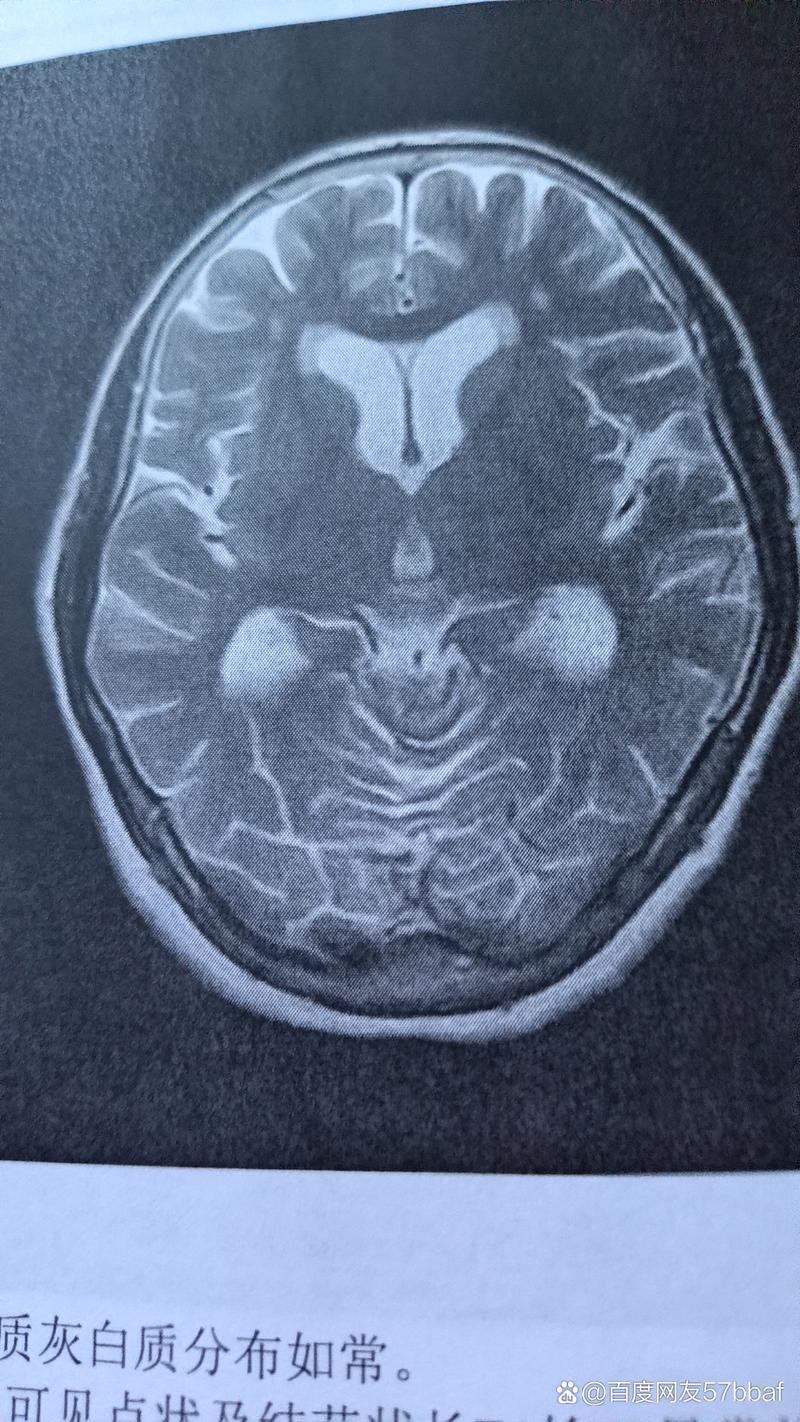

把所有部分合在一起,“双侧脑旁多发缺血脑梗灶”的完整含义是:

在大脑两侧、靠近脑室的区域,出现了多个由于小血管堵塞或缺血导致脑组织坏死的病灶。

这种病灶在临床上有一个更常见的名称,叫做“腔隙性脑梗塞” (Lacunar Infarction)。